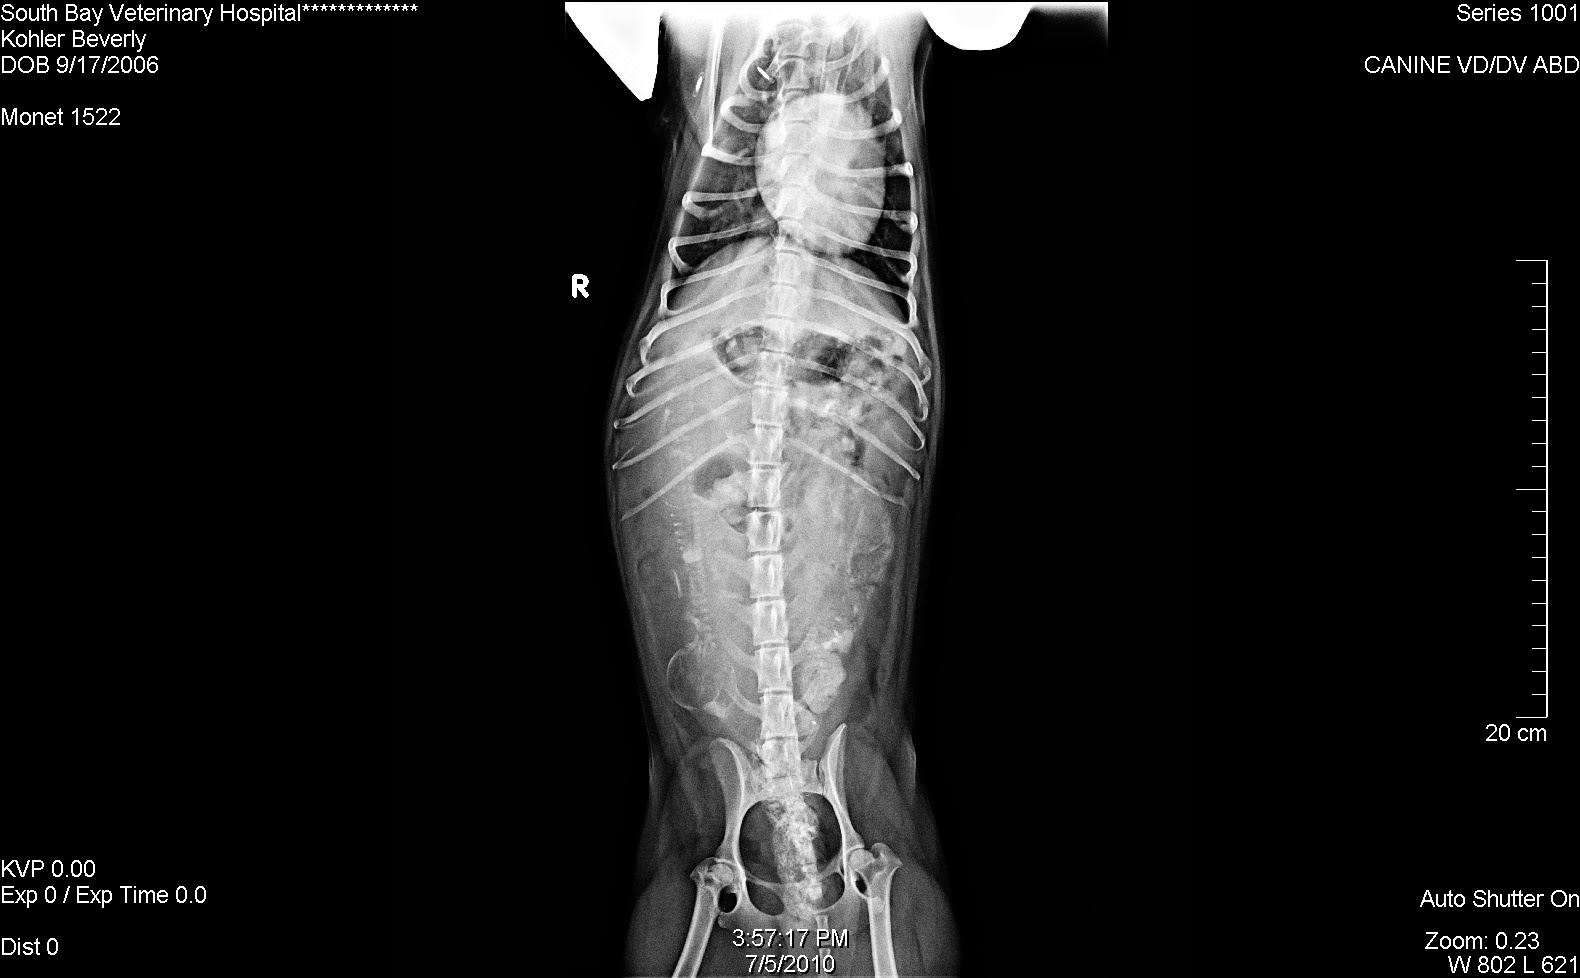

Just like we thought from the ultrasound, there are two puppies. I was getting a little worried that there was only one so I'm relieved to have this news. The vet thinks they have BIG heads. Look for the two spines.